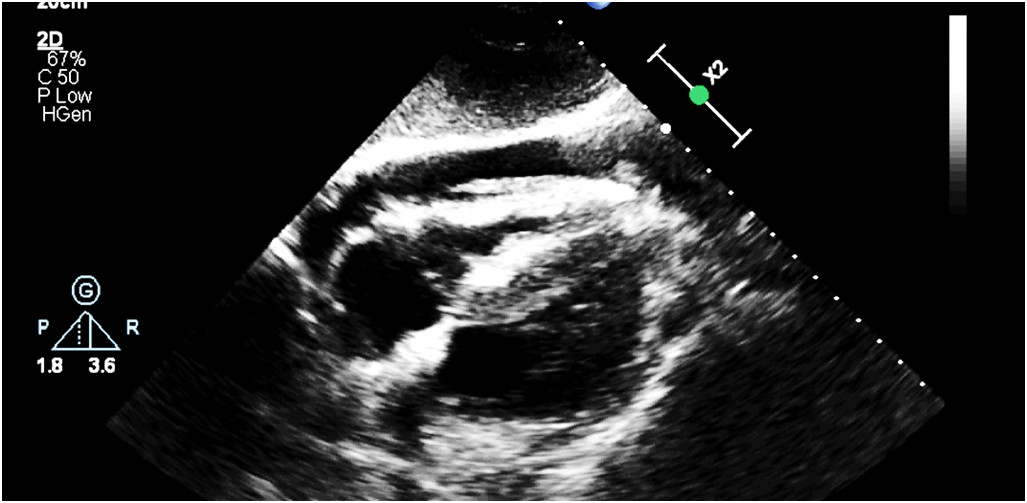

20-letni mężczyzna został ugodzony nożem w klatkę piersiową po lewej stronie. Pacjent w kontakcie logicznym, RR 70/50 HR 120/min. Szmer pęcherzykowy słyszalny po obu stronach klatki piersiowej. Na miejscu zdarzenia ZRM nie zaobserwował dużego krwawienia zewnętrznego. W badaniu FAST w projekcji podmostkowej obraz jak poniżej. Wskaż optymalne dalsze postępowanie: